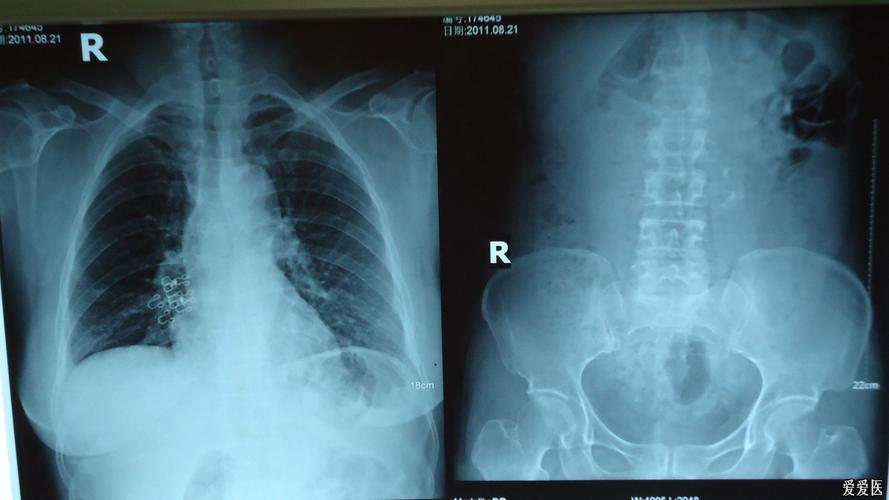

腹部平片显示肠道内积气.腹部增强ct检查发现下腔静脉血栓形成!

腹部平片

腹部立位平片

正常腹部x线平片图

正常腹部平片图片

正常腹部立位片影像图

正常腹部立位平片图片

正常腹部平片影像表现